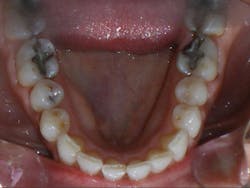

Case 1: 27-year-old male: 2-year clear aligner treatment. There was an estimated 8 mm to 10 mm increase in the transverse measurement. Case and photos courtesy of Dr. Daniel Noor.